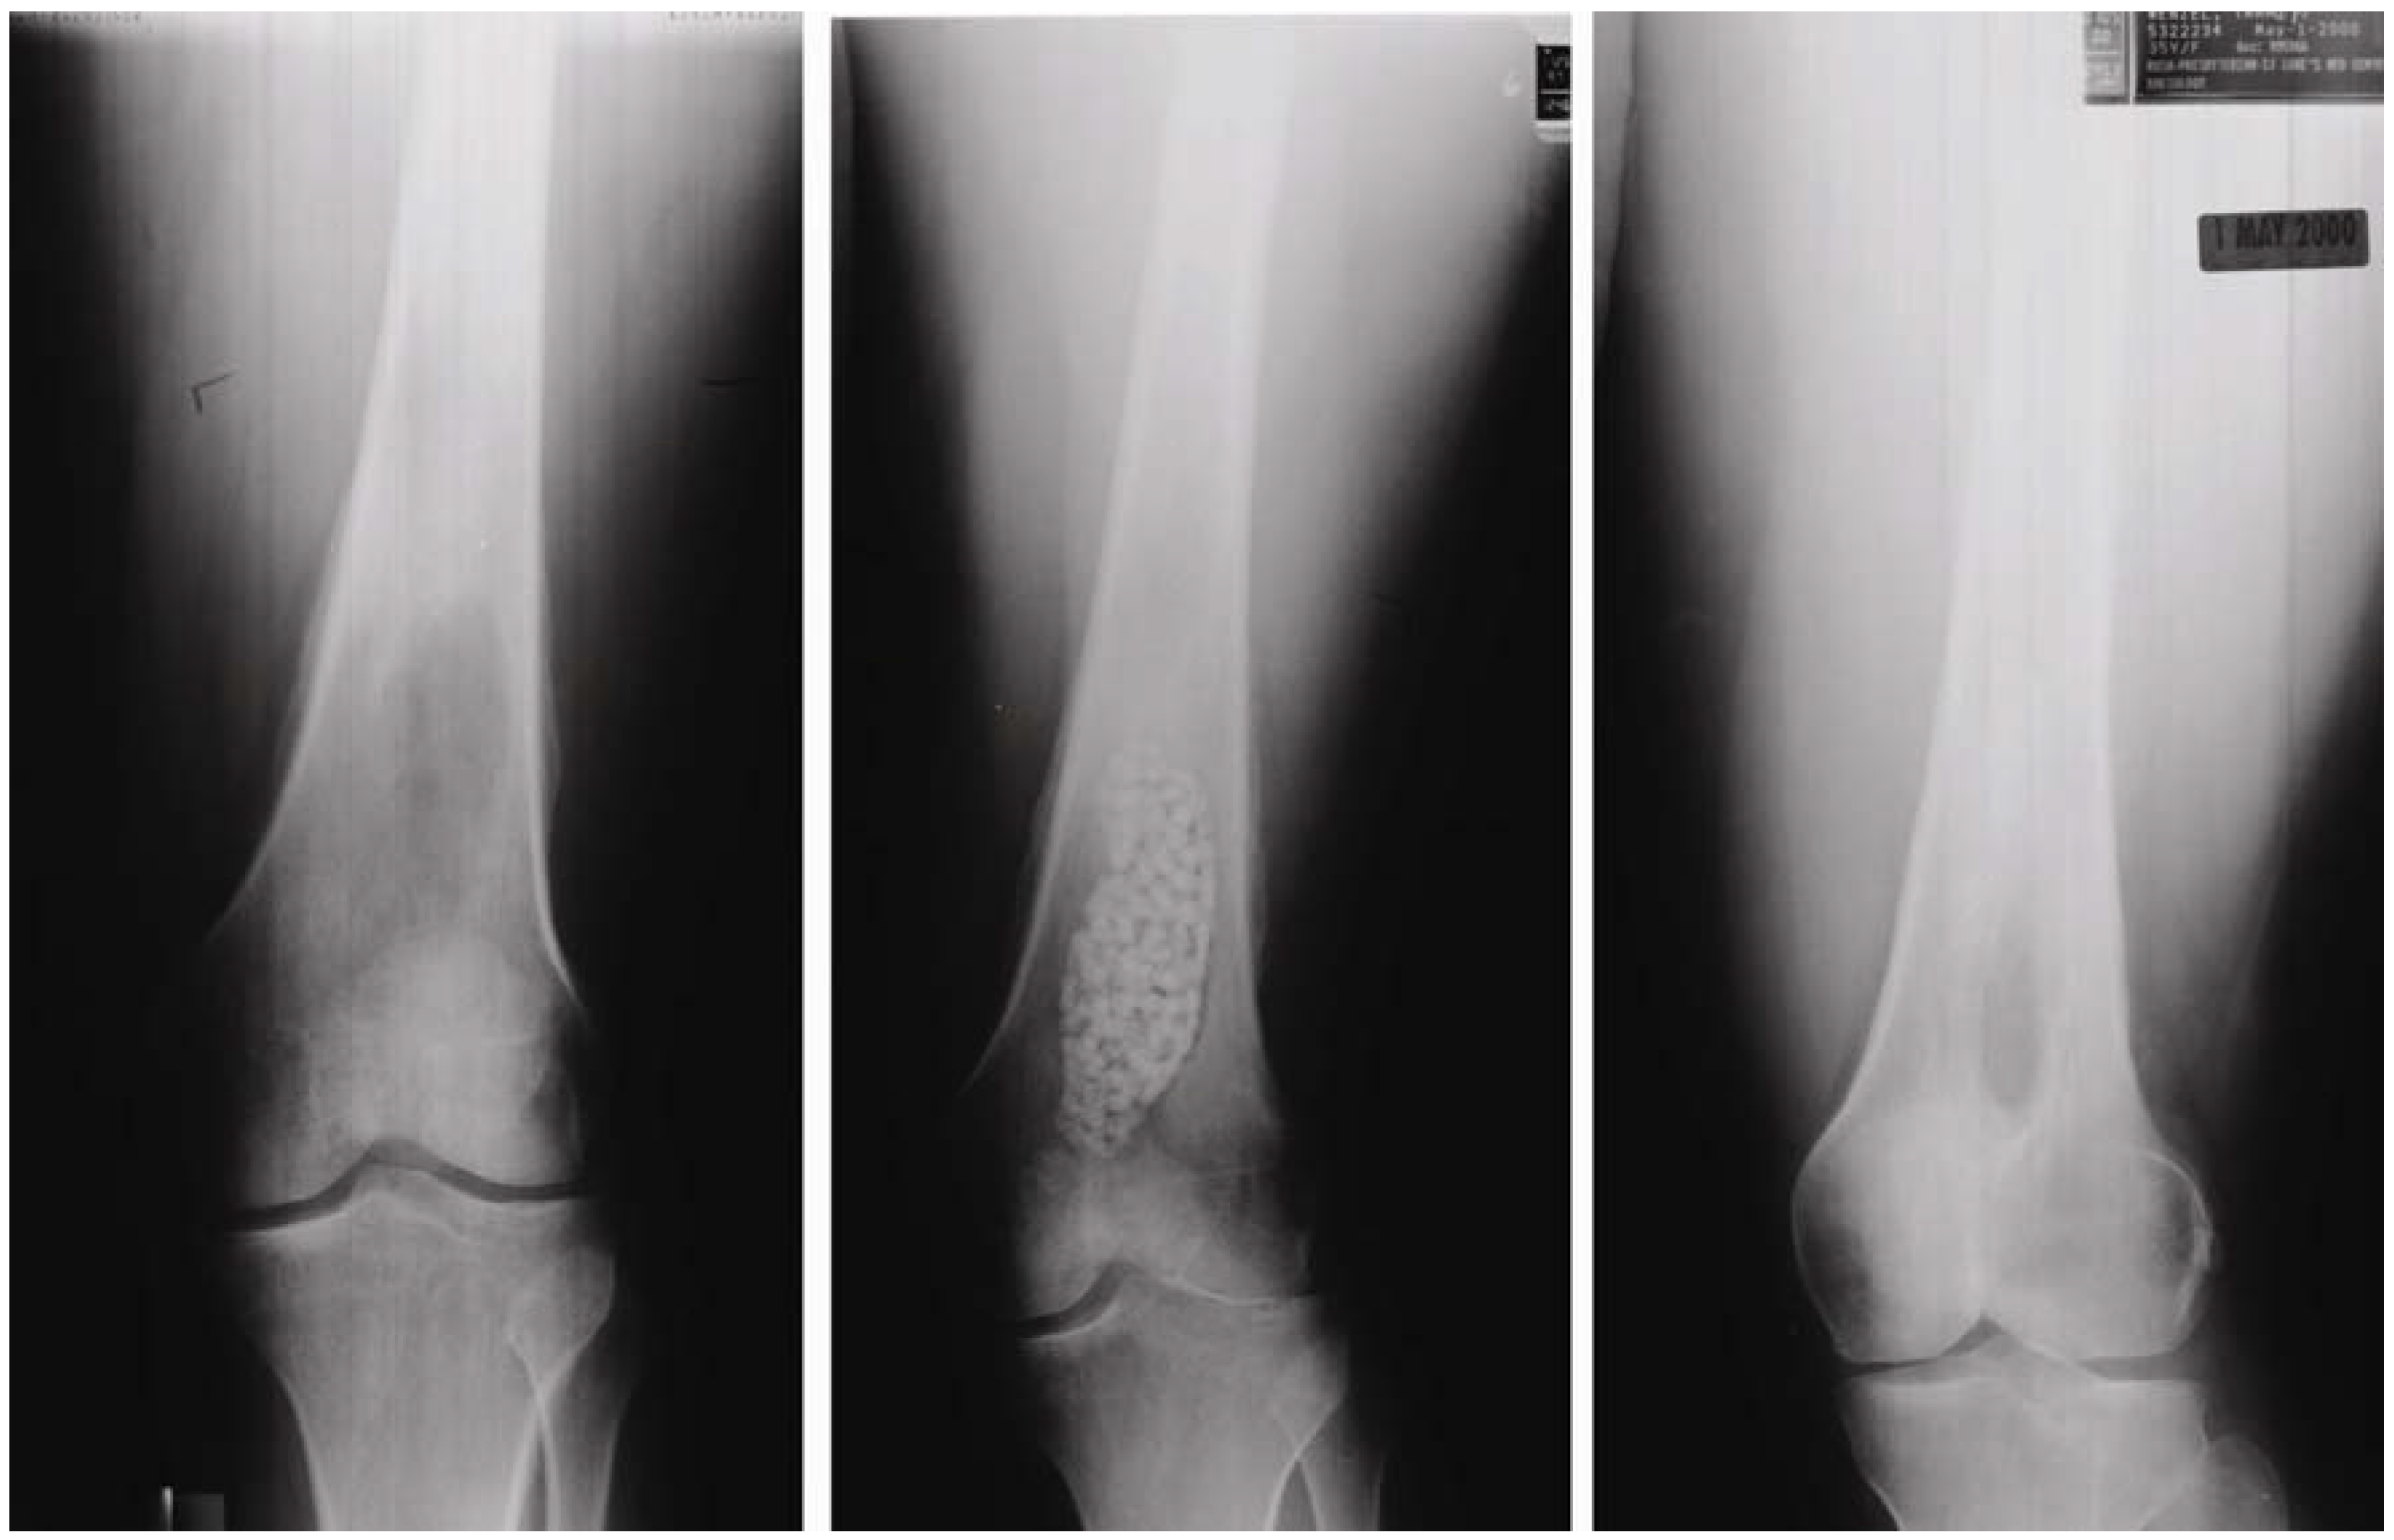

Figure 5. Radiographic assessment of OsteoSet(R) resorbable beads filled into the bone void of a 40-year-old female resulting from osteomyelitis, taken at: preoperation (left), postoperation (middle), and follow-up (right). (Photo courtesy of Wright Medical Technology).

Calcium sulfate sets and harden by phase transformation reaction based on dissolution-precipitation reaction and has the longest history for its use as an artificial bone substitute [12,15,16], for an example, seeFigure 4 and Figure 5. Key properties of calcium sulfate are its rapid and complete resorption with minimal inflammatory response [17,18,19,20]. This is due to the relatively large solubility of calcium sulfate dihydrate. It has also been found that granular hydroxyapatite-like calcium phosphate mineral is deposited on the surface of resorbing calcium sulfate [21,22]. Of course, hydroxyapatite-like calcium phosphate mineral is thought to be formed by the phase transformation reaction based on the dissolution-precipitation reaction. Calcium sulfate dihydrate dissolves and supplies Ca2+ and SO42- to the body fluid since body fluid is undersaturated with respect to calcium sulfate dihydrate. However, once the concentration of Ca2+ is elevated, based on the dissolution of calcium sulfate, the body fluid will be supersaturated with respect to apatite, and thus, apatite crystal is formed. The formed hydroxyapatite-like calcium phosphate mineral may act as an osteoconductive “trellis”. Therefore, osteoconductivity of calcium sulfate is also caused by the superficial phase transformation of calcium sulfate based on dissolution-precipitation reaction.